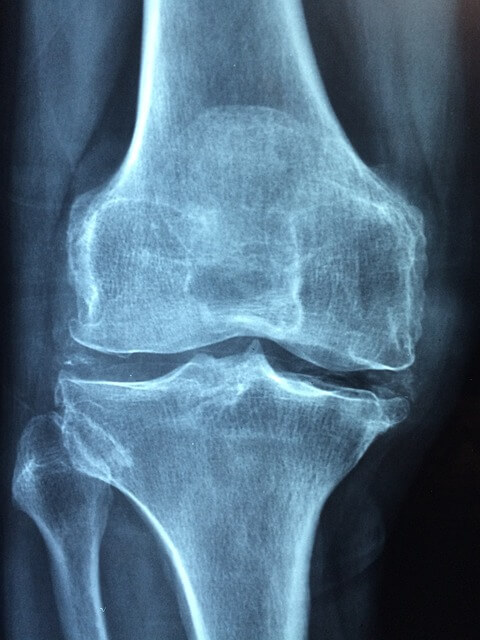

콘드로이친은 연골 활동에 필요한 콜라겐, 히알루론산, 프로테오글리칸, 황산케라틴을 포함하며, 이것은 관절 건강에 필수적인 성분들입니다. 그렇지만 노화가 진행되면 연골 내 콘드로이친은 짧아지고 끊어지며 크기가 감소하는데요, 이로 인해 연골의 탄력이 떨어지고 퇴행성 관절염과 관절 통증을 일으키게 됩니다.

관절과 연골의 주 성분인 콘드로이친은 퇴행성 관절염을 예방해주고 증상을 완화시키는데 도움을 줍니다. 연골이 마모되어 뼈와 뼈 사이가 부딪히며 관절염과 통증이 발생하는데요, 이럴 때 콘드로이친이 연골이 마모되지 않게 도움을 주고, 염증과 통증이 발생하는 것을 방지해 준다고 합니다.